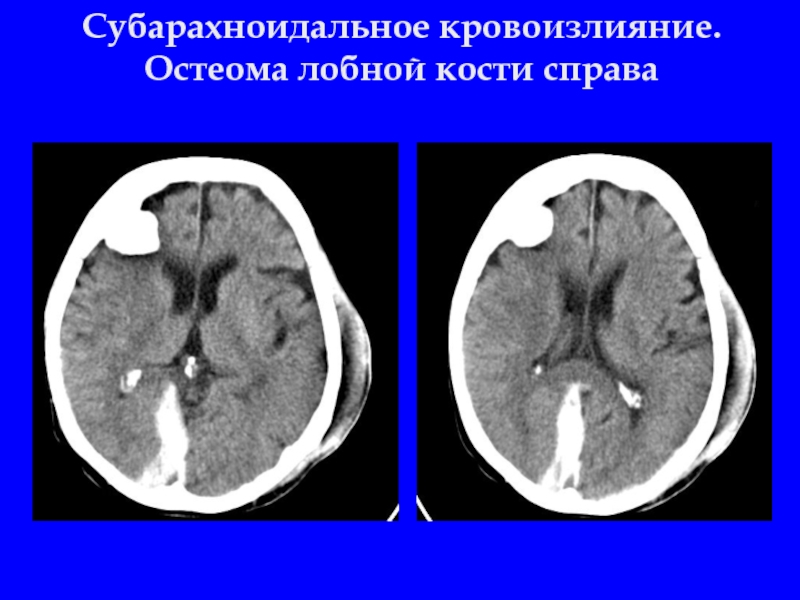

Слайд 32Субарахноидальное кровоизлияние. Остеома лобной кости справа